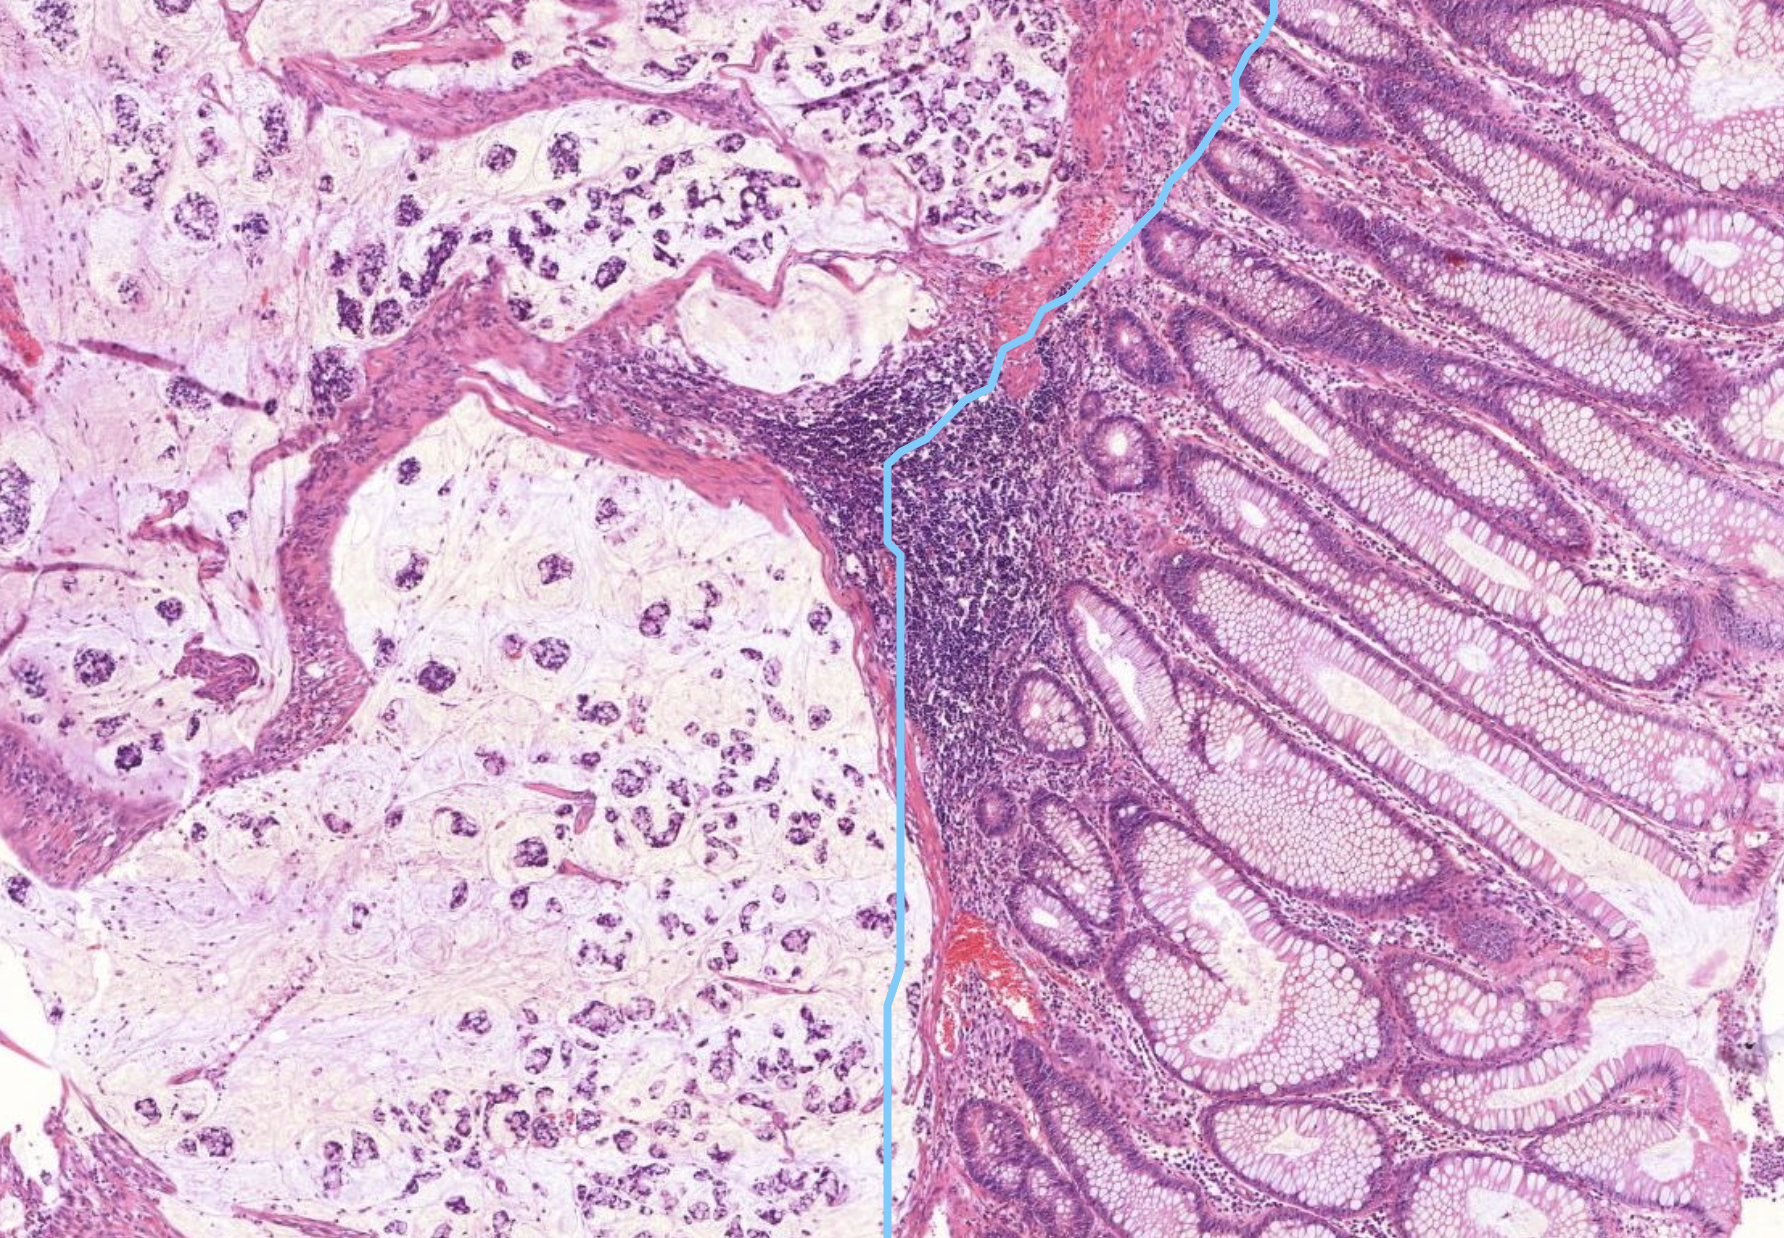

40) Was ist die anatomische Grenze, ab wann wir von einem colonkarzinom sprechen können - was muss durchbrochen sein?

Histopathologisches Bild: Kolonschleimhaut

Bei Karzinomen der Darmschleimhaut (z. B. im Kolon oder Rektum) ist die anatomische Grenze, ab der man von einem invasiven Karzinom spricht, das Überschreiten der Muscularis mucosae..

40) Was sieht man hier im Mittelpuntt?

Es zeigt sich Lymphatisches Gewebe der Colonschleimhaut, sogenannte Pleyer Plaques.

40) Was ist hier links zu sehen?

Colonkarzinom. Links sieht es recht unordentlich aus. Es zeigen sich in kleinen pools auch leukozyten und Fibrin. Hier sind auch super viele Zellen zu sehen .